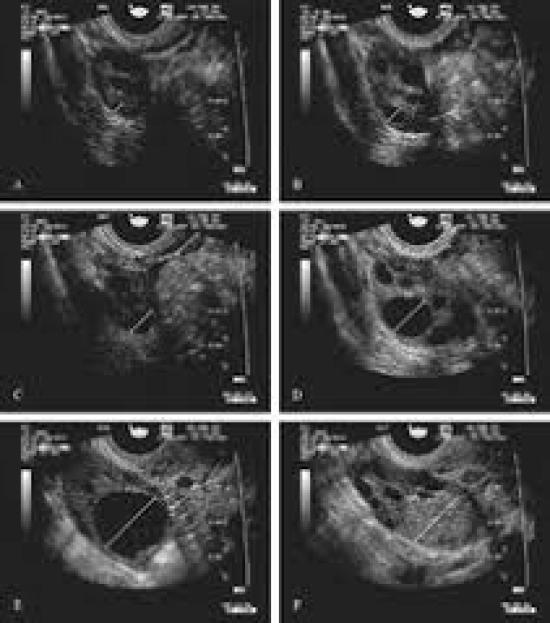

Signs of ovulation on ultrasound. General transvaginal ultrasound is preferred and usually mandatory modality for monitoring follicles. Almost nearing ovulation rapid follicle growth takes place and follicle starts protruding from the ovarian cortex attains a crenated border and it literally explodes to release the ovum along with some antral fluid. Optimal timing of insemination is achieved either by the detection of a luteinizing hormone lh surge through urinary lh testing ulh or by ultrasound monitoring of follicular growth followed by the administration of human chorionic gonadotropin hcg. Ultrasound scanning monitors the growth of a dominant follicle by ultrasound what are the signs of ovulation seen on ultrasound.

In most cases a woman isn t even aware if she is hyperovulating. Two ovulation days including two days of fertile cervical mucus 2 3 days apart. The main indicator of approaching ovulation which can be well seen with ultrasound scanning is a dominant follicle with a diameter of 17 mm or more. However by measuring the maximal diameter of the follicle and observing the morphologic changes within the ovary from follicle to corpus luteum it was possible to detect ovulation in more than 80 of cycles studied.